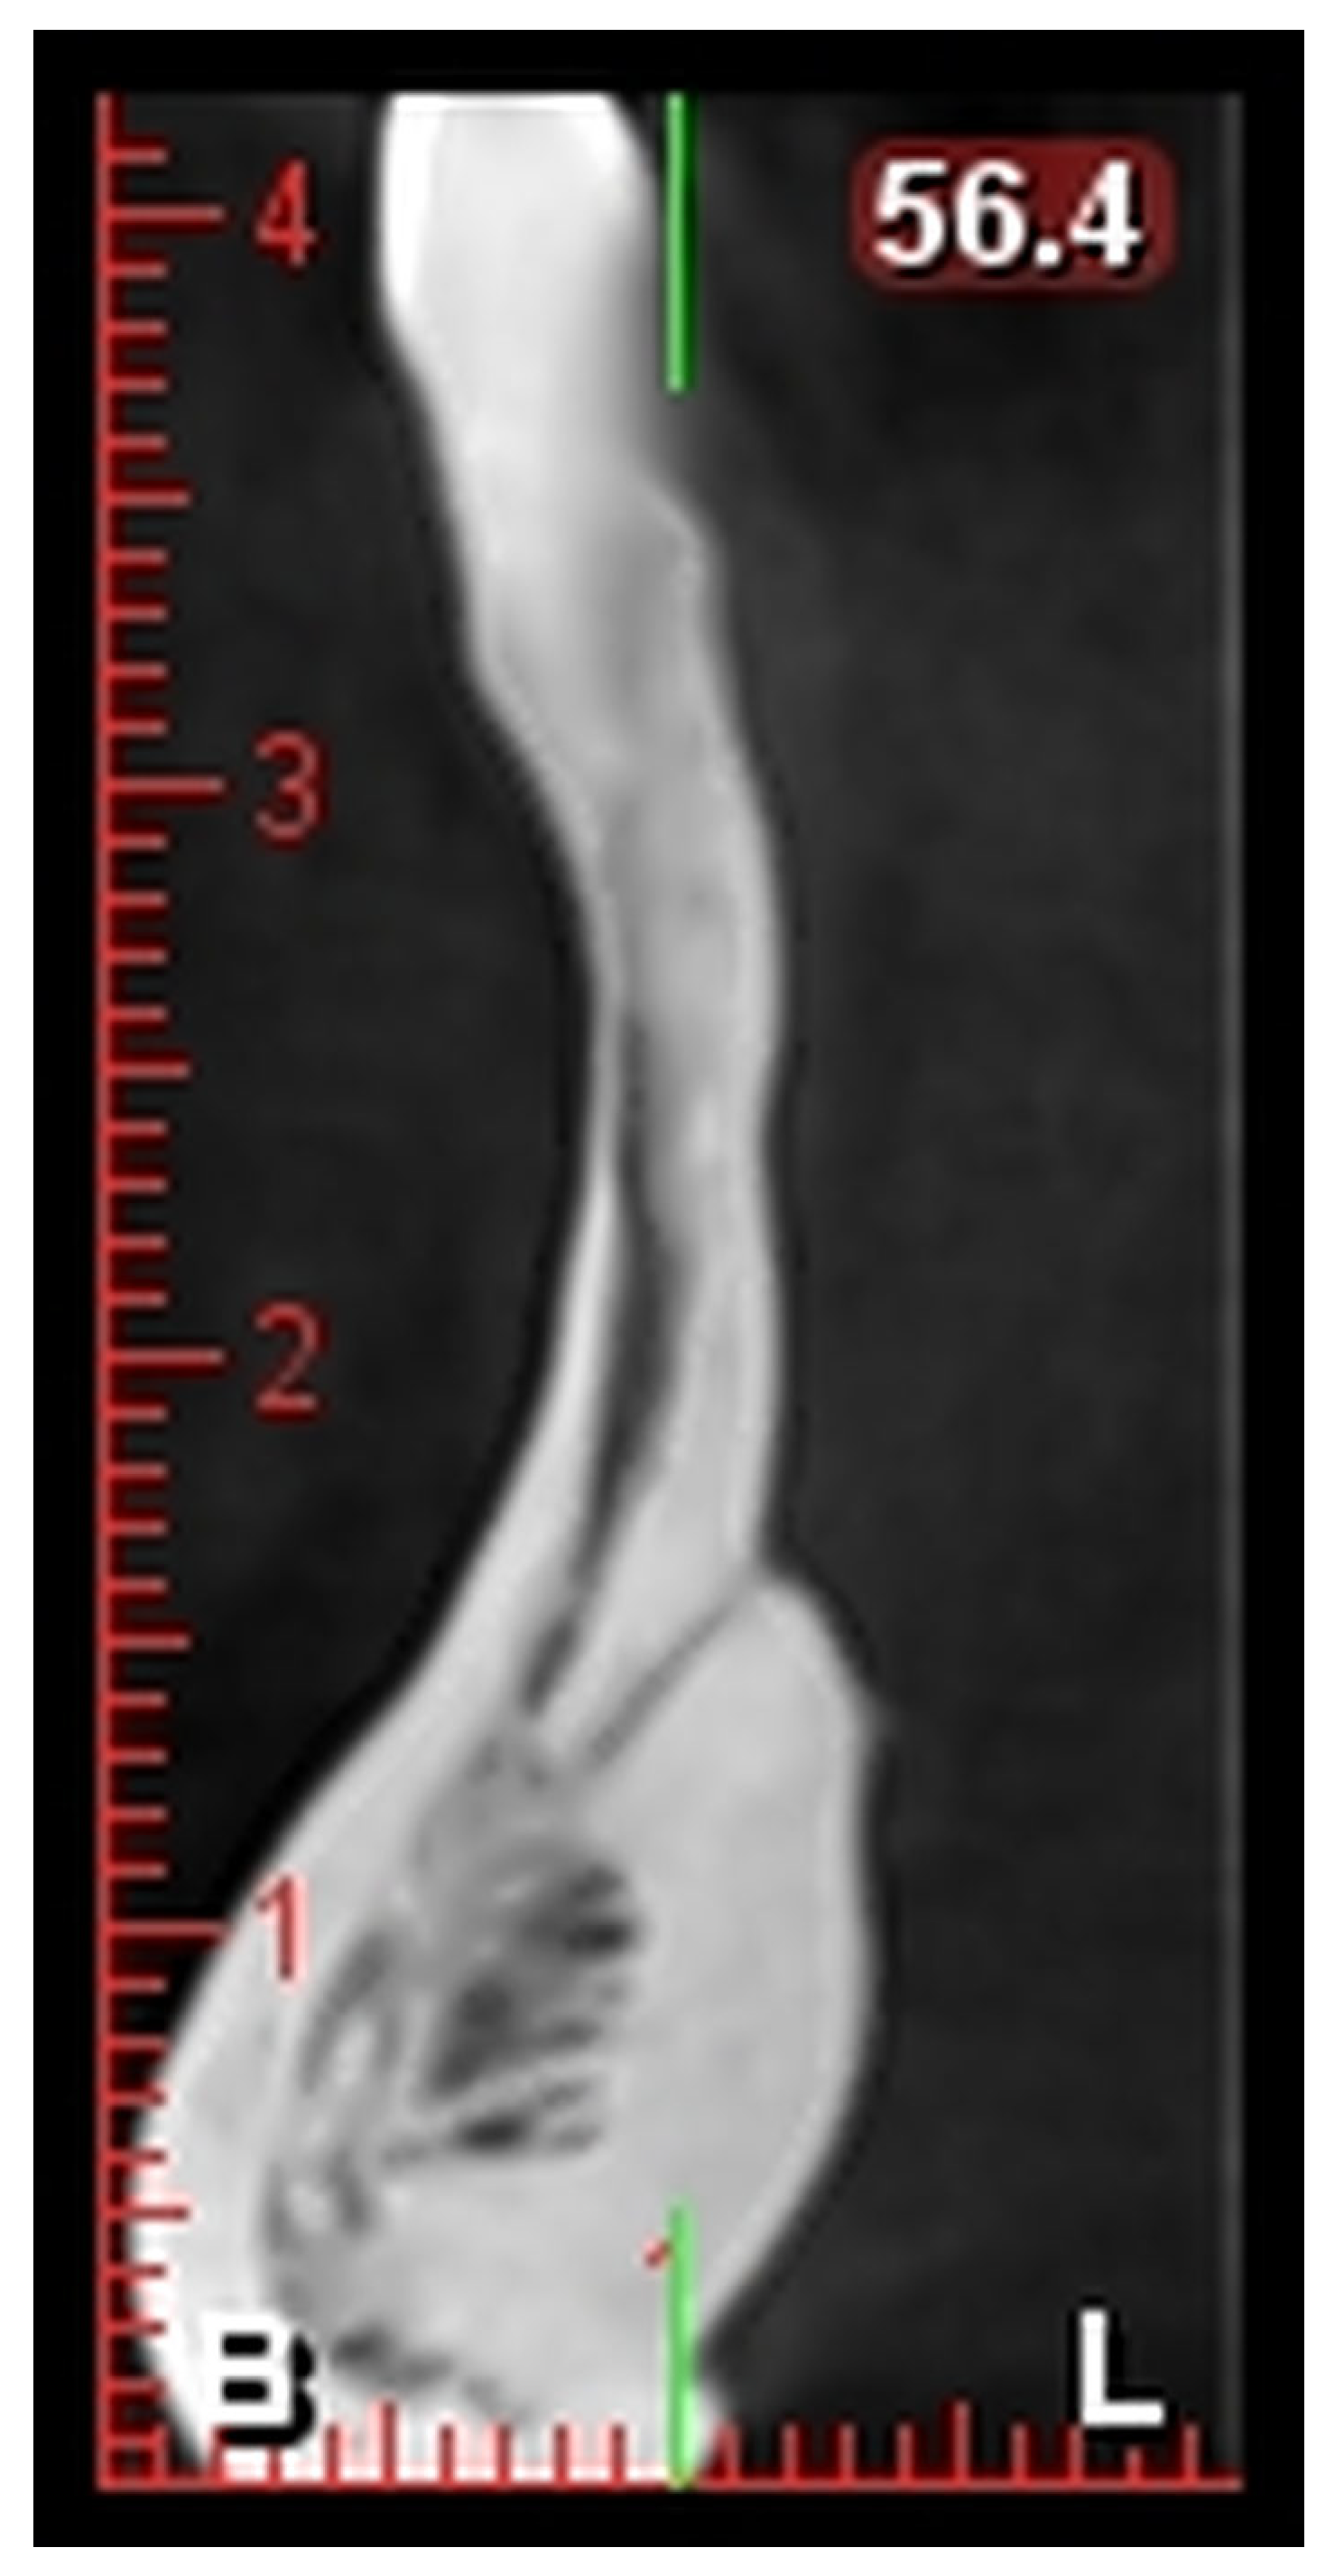

i-CAT Vision software (version 1.9) was used for image reconstruction and multiplanar visualization. The software allowed for the precise localization and measurement of the lingual foramen in the axial, sagittal, and cross-sectional views. Linear measurements, such as the distance from the alveolar crest (L1) and the mandibular border (L2), were performed using a built-in digital caliper tool with a measurement accuracy of ±0.1 mm. All measurements were conducted under standardized viewing conditions by a single trained oral radiologist and were performed twice with an interval of 15 days to maintain consistency.

L1: Distance from the alveolar crest to the lingual foramen (

Figure 1).

L2: Distance from the lingual foramen to the lower mandibular border (